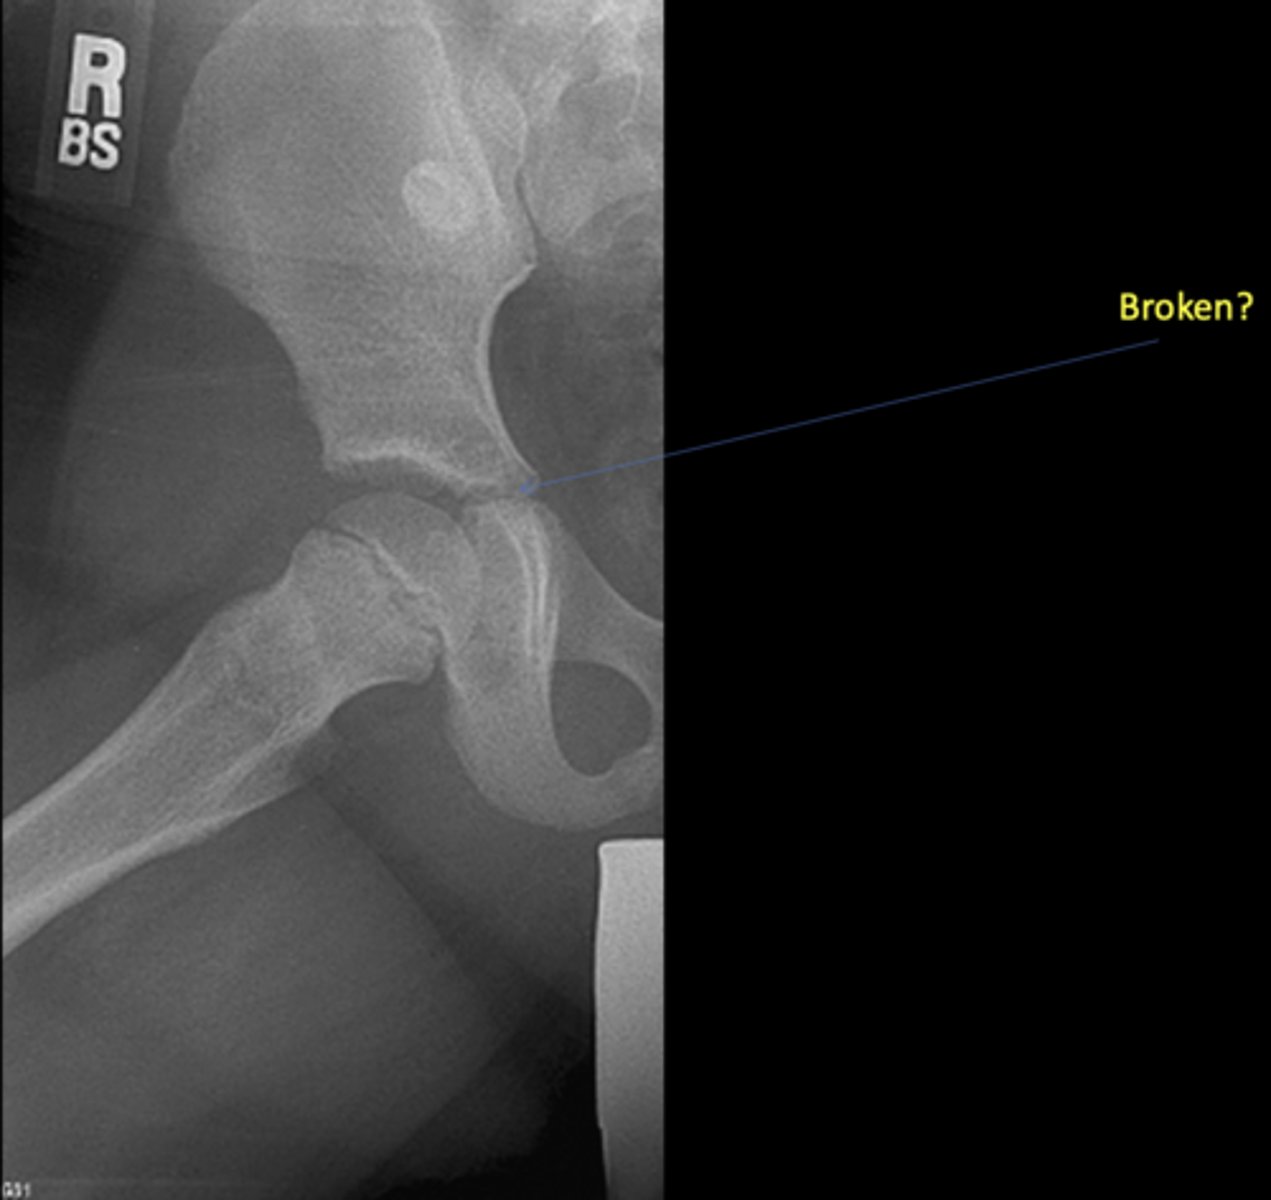

No - growth plate in a child

Broken?

<p>Broken?</p>

New cards